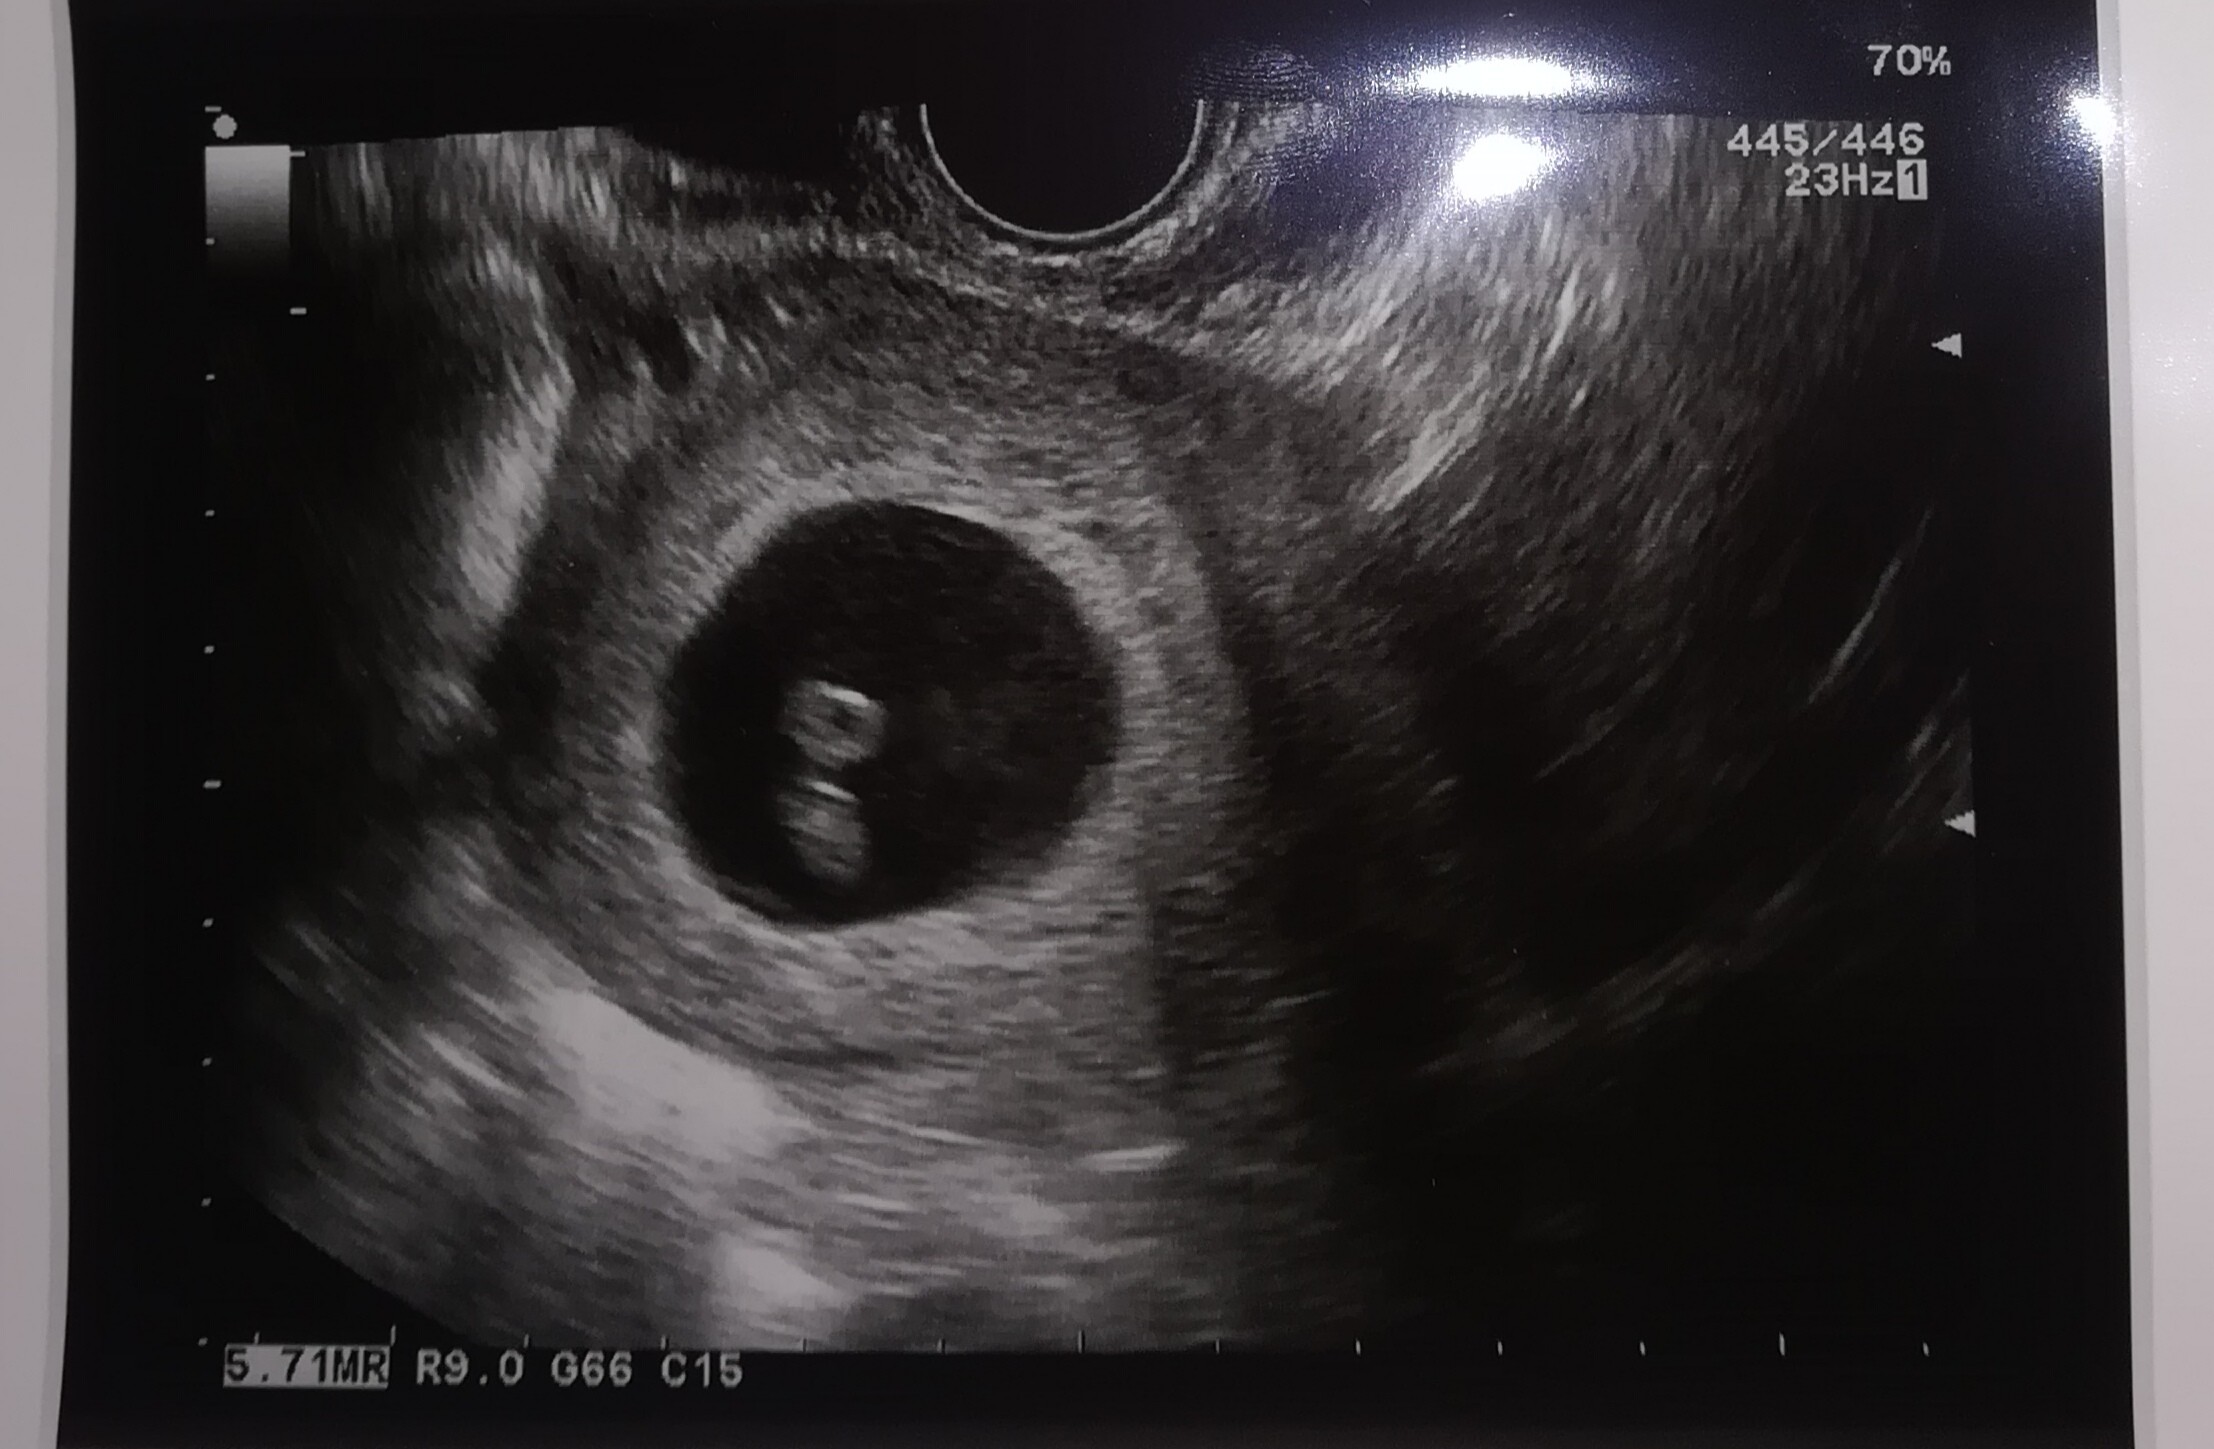

Tak,w piątek pojechałam z plamieniem a na usg stwierdzono brak akcji serca . Dostałam skierowanie do szpitala,i w razie gdyby samo "ruszyło" mam jechać odrazu ale póki co czekam... To chyba jeszcze gorsze to czekanie , chyba wolę to mieć za sobą [emoji25][emoji2731]